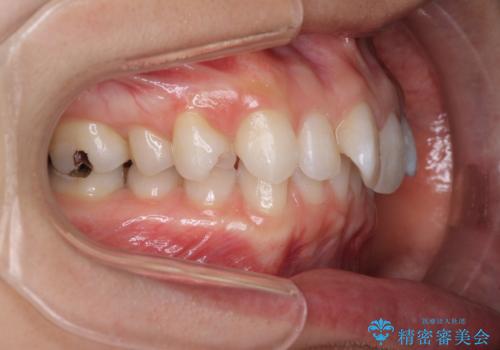

深い咬み合わせと奥歯のむし歯 総合歯科治療

- 奥歯の虫歯と前歯のデコボコや突出感を気にして来院された患者様です。

矯正治療後は、奥歯の虫歯や銀歯を補綴・修復治療することとしました。

上顎歯列を下顎に対して4mmほど移動させる必要があったため、治療は長期化することが予想されましたが、患者様にはこちらの期待以上にゴムかけなどに協力いただき、補綴治療も含めて2年強で終えることができました。